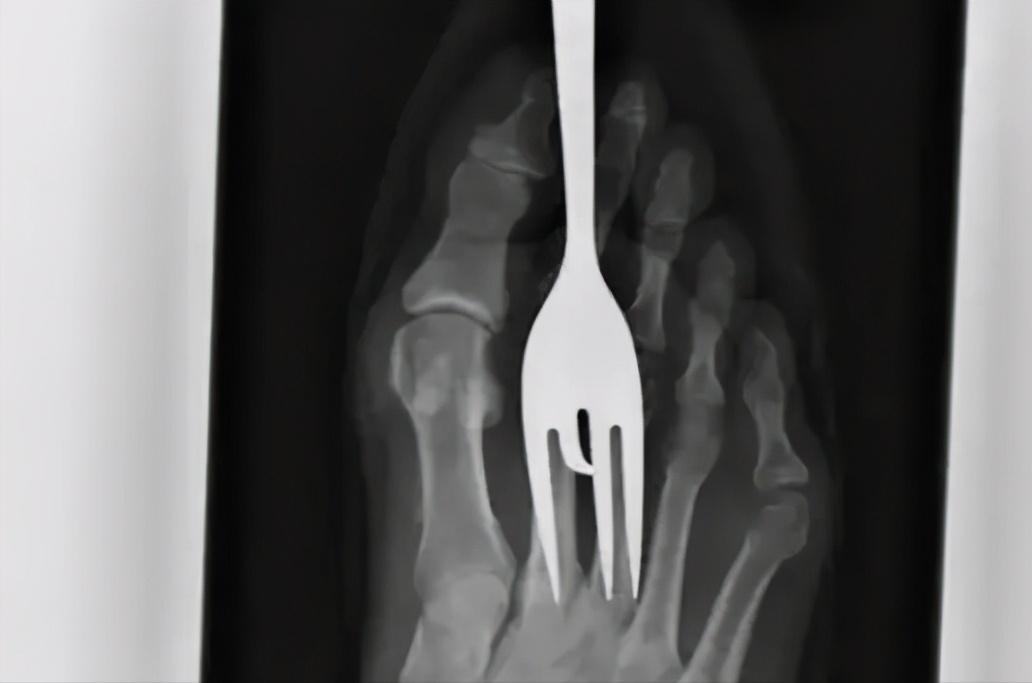

又或者使用餐具时,你的脚被叉子戳穿了...